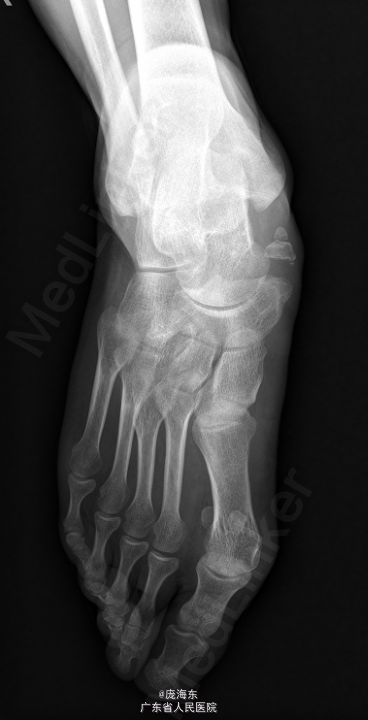

患者,男,35岁,因“右足内侧肿块伴疼痛6年,加重1个月”入院。

右足平足,右足舟骨内侧骨性突起明显,局部压痛(+),沿肌腱走行压痛,无局部红肿,右踝关节、右足趾伸屈活动无明显受限,足背动脉可及。远端血循良好,感觉正常。当地医院X线:右足副舟骨,建议进一步检查。

初步诊断: 1.右足胫后肌腱炎;2、右足副舟骨痛。在全身麻醉下行“ 右足副舟骨切除+胫后肌腱重建术”. 。内足舟骨处作一横行长约5cm的切口,依次切开皮肤,皮下组织及筋膜层,暴露胫后肌腱处,见副舟骨形成,副舟骨及舟骨表面散在白色斑点样改变,副舟骨局部可活动,关节囊内淡草黄积液,见胫后肌腱粘连增生肥大,切除副舟骨,游离趾长屈肌腱并远端切断,足舟状骨处打入一锚钉,将胫后肌腱处锚线缝合固定,足舟骨局部转孔,穿过铆线,将趾长屈肌腱缝合于足舟骨处,再将胫后肌腱及趾长屈肌腱固定缝合,活动足部见肌腱缝合牢固,冲洗,逐层缝合,无菌包扎。